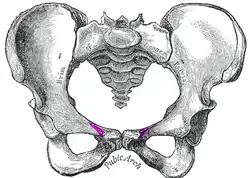

Female pelvis. Pectineal line in purple slightly lateral to midline of bottom of central opening. | |